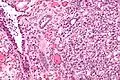

| Micrograph of a nephrogenic adenoma. H&E stain. | |

Nephrogenic adenomas are diagnosed under the microscope by pathologists. Microscopically the tumor shows closely packed small tubular structures in edematous stroma. The tubules show considerable variation in size and shape resembling convoluted tubules of the kidney. The single layer of cells lining the tubules are cuboidal with a scant to moderate amount of cytoplasm. In some areas they may have a hobnail appearance. [2]

Low mag High mag

High mag